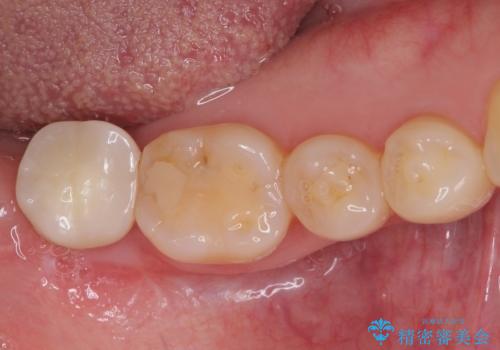

ストローマン社のSLActiveというインプラントを使用し、インプラント埋入からクラウンが装着されるまで3ヶ月弱という短期間で終えることができました。

咬み心地はもちろん、清掃性もご自分の歯とほとんど変わらない状態となり、患者様には大変満足していただきました。